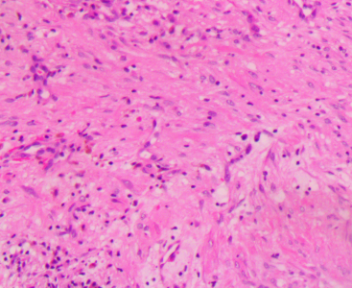

上臂肿物

性别

男

年龄

44岁

临床诊断

肿物性质待查

一般病史

无

标本名称

大体所见

灰白不规则软组织1块1.5x1.5x1cm。

图1